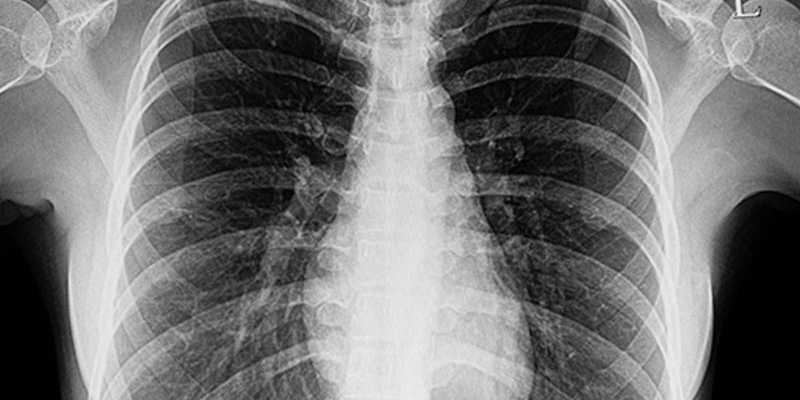

In 2019, the CDC investigated thousands of lung injury cases and more than 40 deaths that were likely related to vaping.